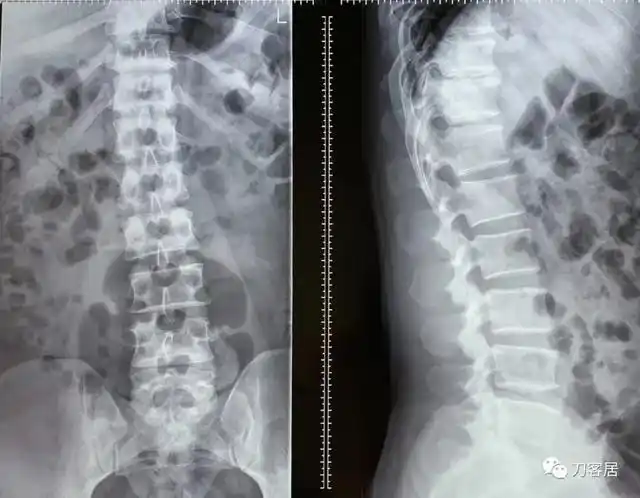

20岁腰间盘突出微创转开放手术后真实记录日记; - 知乎

腰椎间盘突出微创手术第八天